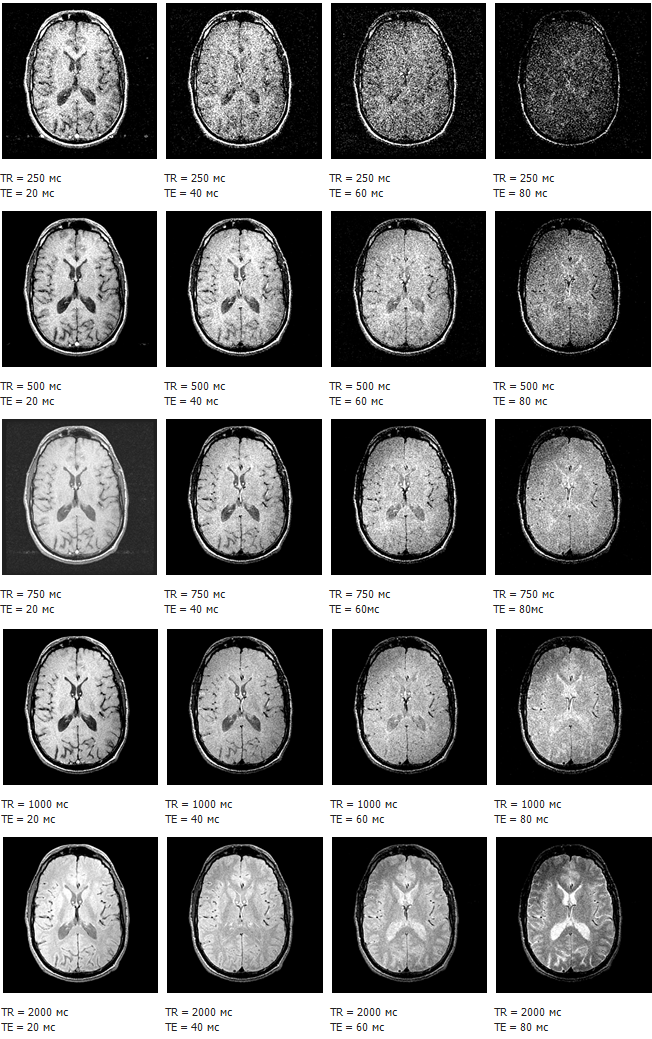

Важными техническими параметрами ИП, часто используемыми при описании данных, являются:

Время повторения TR (Time Repetition) - промежуток времени между началами импульсных последовательностей.

Время эха ТЕ (Time Echo) - промежуток времени между первым импульсом последовательности и измерением ответного сигнала.

Оператор томографа подбирает данные значения (наряду с другими параметрами) для достижения максимального контраста изучаемых тканей.